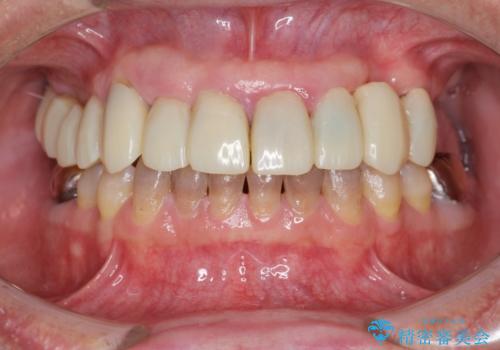

- 他院で上顎は全て抜歯し、入れ歯にする必要があると言われ相談に来院されました。

検査の結果、重度の歯周病であることから保存が難しい歯は抜歯を行いインプラントを、残すことが可能な歯には再生治療を含めた歯周病治療を行いより多くの歯を残す歯周病治療を計画します。

上顎は、残っている前歯も揺れがあり残すためにはクラウンでつなぐ歯周補綴が必要な状態です。

また咬合負担に不安のある前歯を助けるためにも、臼歯部にインプラント補綴を行いしっかりとかめる状態とすることも大切です。